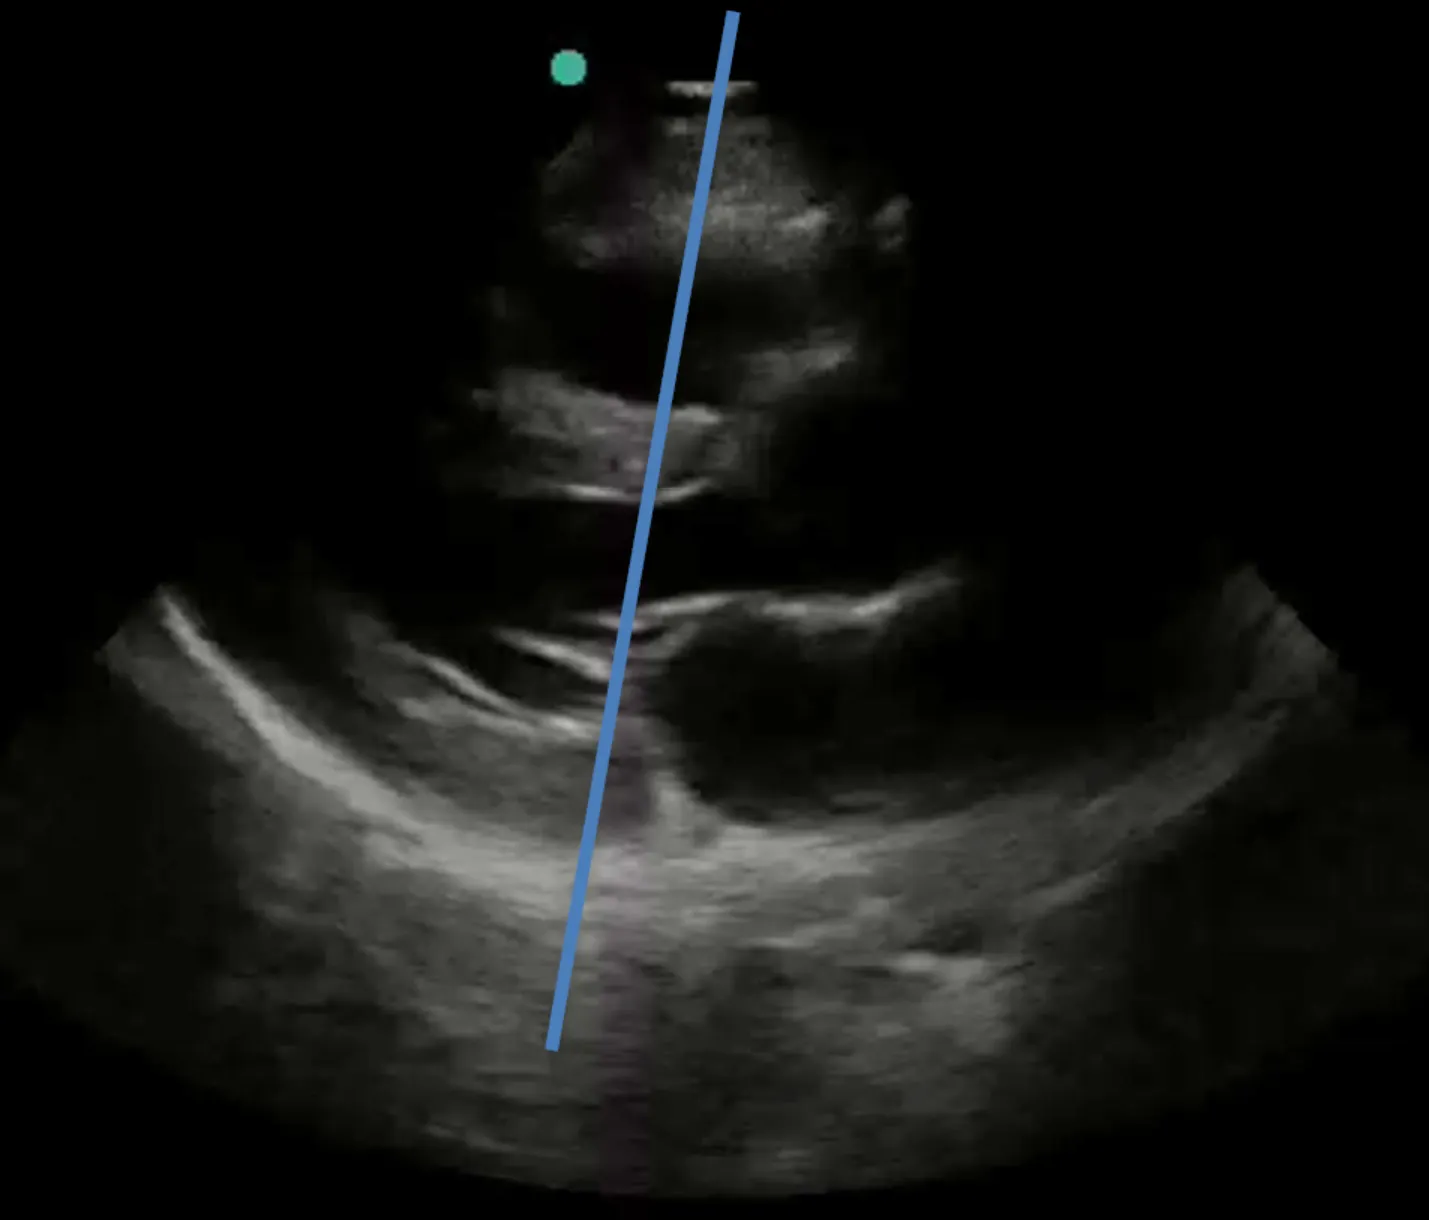

1. E point septal seperation (EPSS)